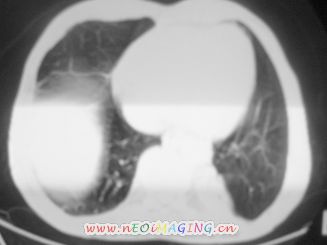

以下是引用南沙在2007-10-7 10:44:00的发言:[br]左下肺不张.[br]肺癌可能性大?

以下是引用卜一在2007-10-7 9:38:00的发言:[br]左下肺胸膜下团片影,内见含气支气管像,临近胸膜未见增厚。多考虑:1 左下肺炎症,建议消炎后复查!2 不除外肺隔离症合并感染!